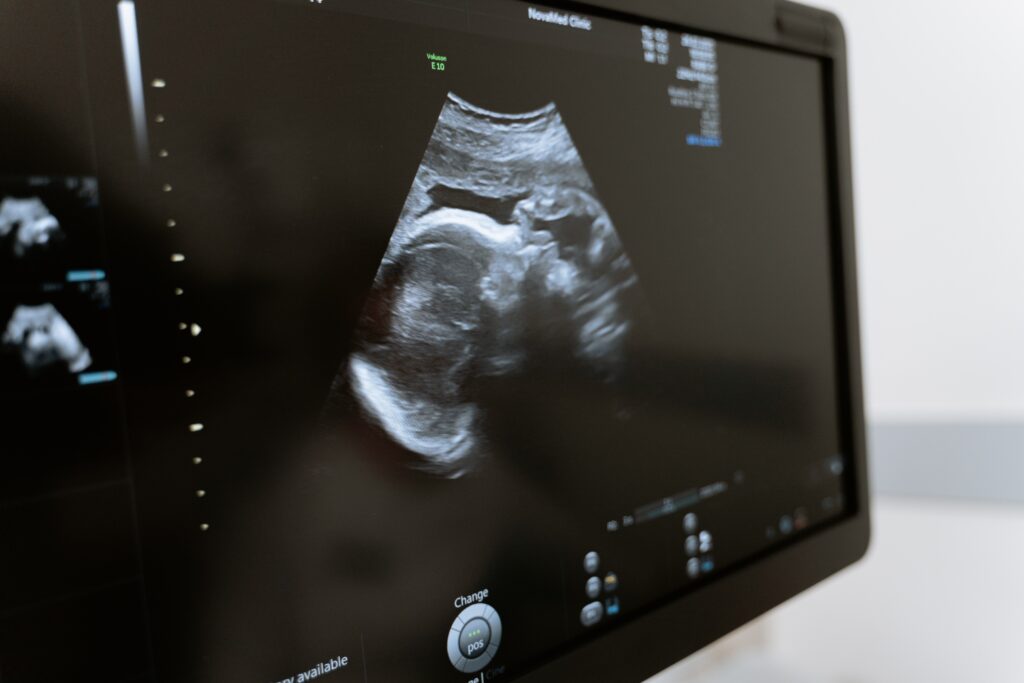

Fetal Ultrasound

Fetal Ultrasound is a key component of our Fetal Medicine specialty. Using state-of-the-art ultrasound technology, our experienced sonographers perform detailed scans to monitor fetal growth, and development, and detect any potential abnormalities.

This non-invasive procedure provides valuable insights into the health and progress of your baby.